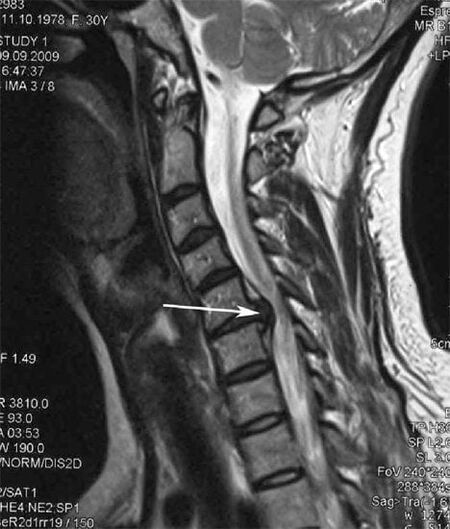

Nas fases iniciais, a osteocondrose detéctase mediante resonancia magnética. Máis tarde, a patoloxía pódese diagnosticar mediante radiografía. Nas radiografías da columna cervical nótanse unha redución da distancia entre as vértebras, cambios patolóxicos nas articulacións facetarias e osteofitose.

Moitas persoas quéixanse de que non poden virar o pescozo por mor dunha dor intensa cando de súpeto levantan algo pesado. Este fenómeno indica o desenvolvemento dunha hernia discal. A causa da dor nas costas, no pescozo e nas extremidades superiores é o pinchazo dunha das raíces nerviosas que sae da medula espiñal.

| Osteocondrose cervical | A aparición de cambios patolóxicos nun ou máis segmentos de movemento da columna vertebral. Mobilidade prexudicada da columna vertebral, desenvolvemento de síndromes de dor miofascial e beliscar as raíces da columna vertebral | Dor, parestesia e trastornos motores na zona do pescozo, estendéndose á parte posterior da cabeza e aos membros superiores. Detección de cambios característicos na columna vertebral en imaxes de resonancia magnética e de raios X (osteofitos, distancia vertebral reducida, signos de dano nas articulacións intervertebrais) |